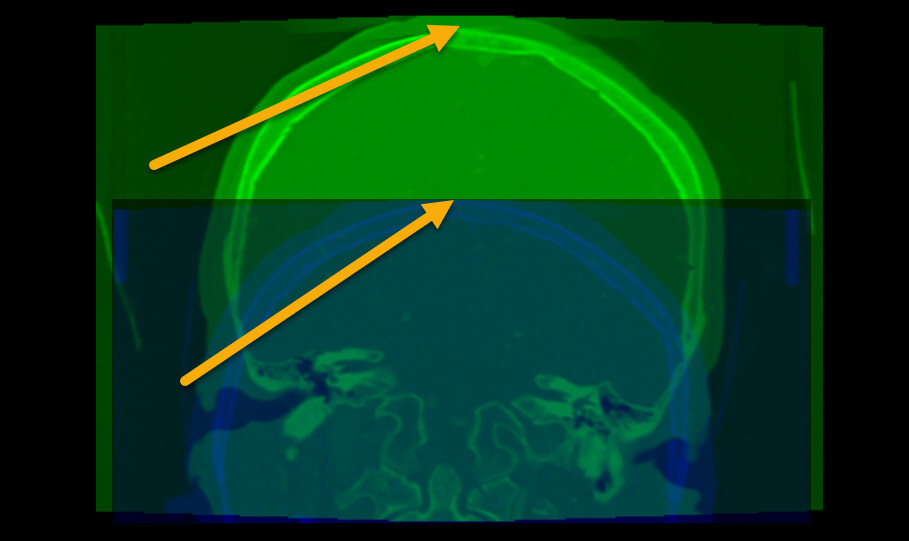

Interesting. For me, Elastix registered the images you shared with the rigid preset.

result: